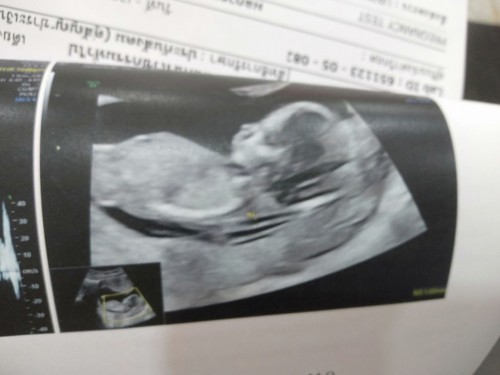

ท้องได้3เดือน 6วันแต่น้ำหนักไม่ขึ้นเลย หรือว่าลงลูก